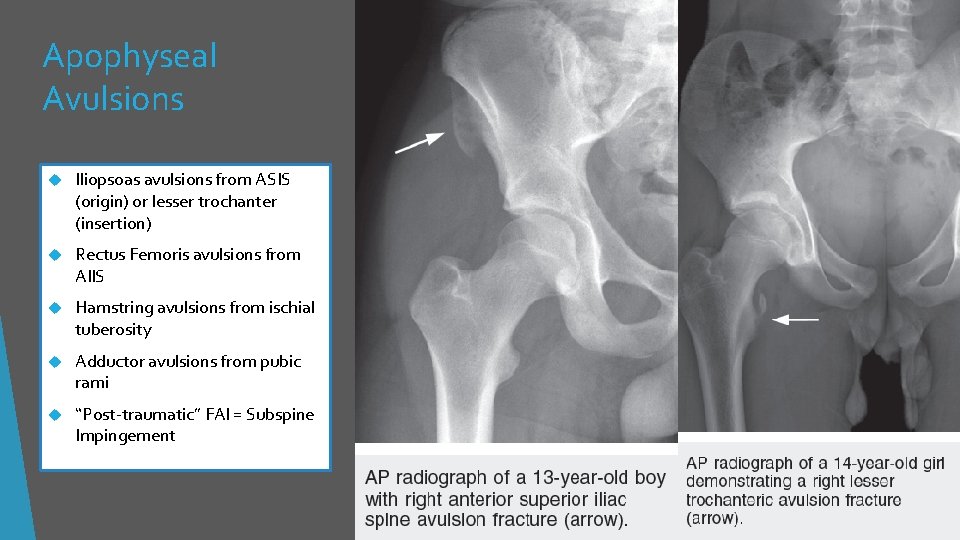

Apophyseal Avulsions Iliopsoas avulsions from ASIS (origin) or lesser trochanter (insertion) Rectus Femoris avulsions from AIIS Hamstring avulsions from ischial tuberosity Adductor avulsions from pubic rami “Post-traumatic” FAI = Subspine Impingement